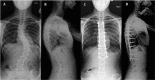

Background: Technological advances, including navigation, have been made to improve safety and accuracy of pedicle screw fixation. We evaluated the accuracy of the virtual screw placement (Stealth projection) compared to actual screw placement (intra-operative O-Arm) and examined for differences based on the distance from the reference frame.

Methods: A retrospective evaluation of prospectively collected data was conducted from January 2013 to September 2013. We evaluated thoracic and lumbosacral pedicle screws placed using intraoperative O-arm and Stealth navigation by obtaining virtual screw projections and intraoperative O-arm images after screw placement. The screw trajectory angle to the midsagittal line and superior endplate was compared in the axial and sagittal views, respectively. Percent error and paired t-test statistics were then performed.

Results: Thirty-one patients with 240 pedicle screws were analyzed. The mean angular difference between the virtual and actual image in all screws was 2.17° ± 2.20° on axial images and 2.16° ± 2.24° on sagittal images. There was excellent agreement between actual and virtual pedicle screw trajectories in the axial and sagittal plane with ICC = 0.99 (95%CI: 0.992-0.995) (p<0.001) and ICC= 0.81 (95%CI: 0.759-0.855) (p<0.001) respectively. When comparing thoracic and lumbar screws, there was a significant difference in the sagittal angulation between the two distributions. No statistical differences were found distance from the reference frame.

Conclusion: The virtual projection view is clinically accurate compared to the actual placement on intra-operative CT in both the axial and sagittal views. There is slight imprecision (~2°) in the axial and sagittal planes and a minor difference in the sagittal thoracic and lumbar angulation, although these did not affect clinical outcomes. In general, we find that pedicle screw placement using intraoperative cone beam CT and navigation to be accurate and reliable, and as such have made it a routine part of our spine practice. This study was approved by the University of Minnesota IRB (#1303E30544).